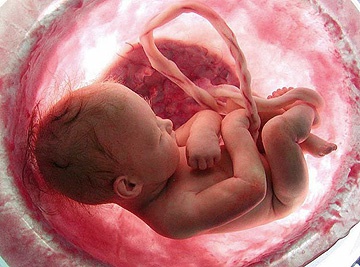

Как выглядит ребенок на 39 неделе беременности

Ребенок выглядит как младенец на картинках: кожа розовая, пушковые волосы могут остаться только в складочках. Ногти острые и выходят за край пальчиков. Кости черепа податливы, что позволяет головке проходить через родовые пути. Рост плода увеличивается за счет удлинения конечностей и туловища. Набор веса может приостановиться, чтобы облегчить роды.

Плод плотно окружен стенками матки, конечности согнуты и прижаты к телу. Предлежащая часть опускается в полость таза и не меняет своего положения до родов. Активные движения замедляются из-за недостатка пространства, но количество шевелений должно оставаться не менее 10 за 12 часов. Средний вес малыша на этом сроке составляет 3 кг, рост — 50 см.